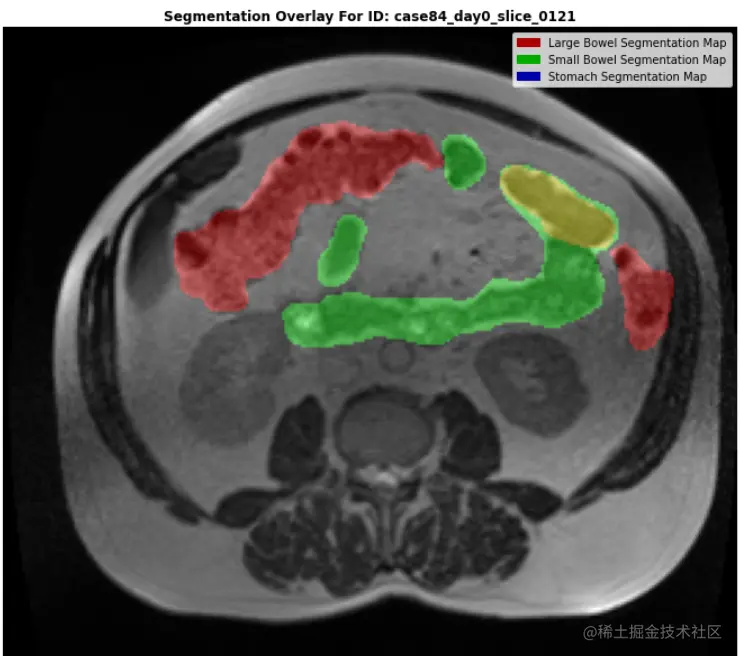

4.6 MASK数据集创建、类重叠和 MASK HEATMAP

确定MASK是否相互重叠(multilabel)或不重叠(multiclass)非常重要。为此,我们将快速创建 npy 文件的数据集。在这个创建过程中,我们将检查重叠。

观察

• 存在重叠,虽然并不常见,但某些图像显示出高度重叠。

• 这意味着我们不能将问题描述为简单的分类语义分割。

• 我们必须将问题描述为多标签语义分割

• 这意味着我们的MASK将采用以下形式 -->

• 通道维度是每个分割类型的二进制掩码

• 这将允许MASK重叠

注意以下绘制的图像:

• 在下面的检查图像中,我们可以看到小肠的一部分完全位于大肠的较大部分内。

• 这说明了为什么将其视为多标签语义分割如此重要!